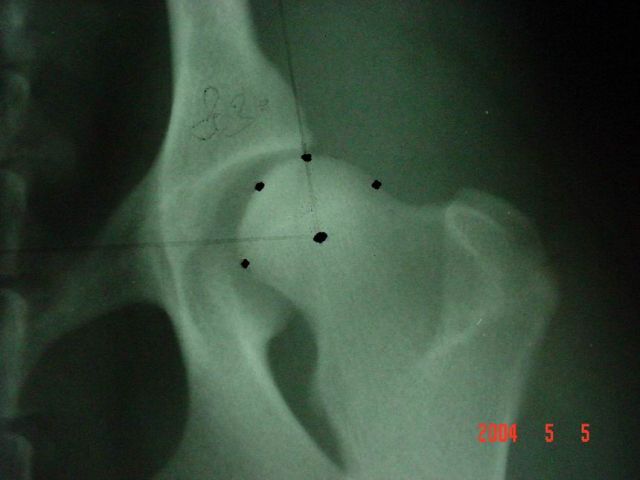

Kattintás=nagyításMajdnem normál az ízület, ha kisebb, mint 105°, de enyhén divergál az ízületi rés, vagy ha nem divergál, de 100°-105° közötti.